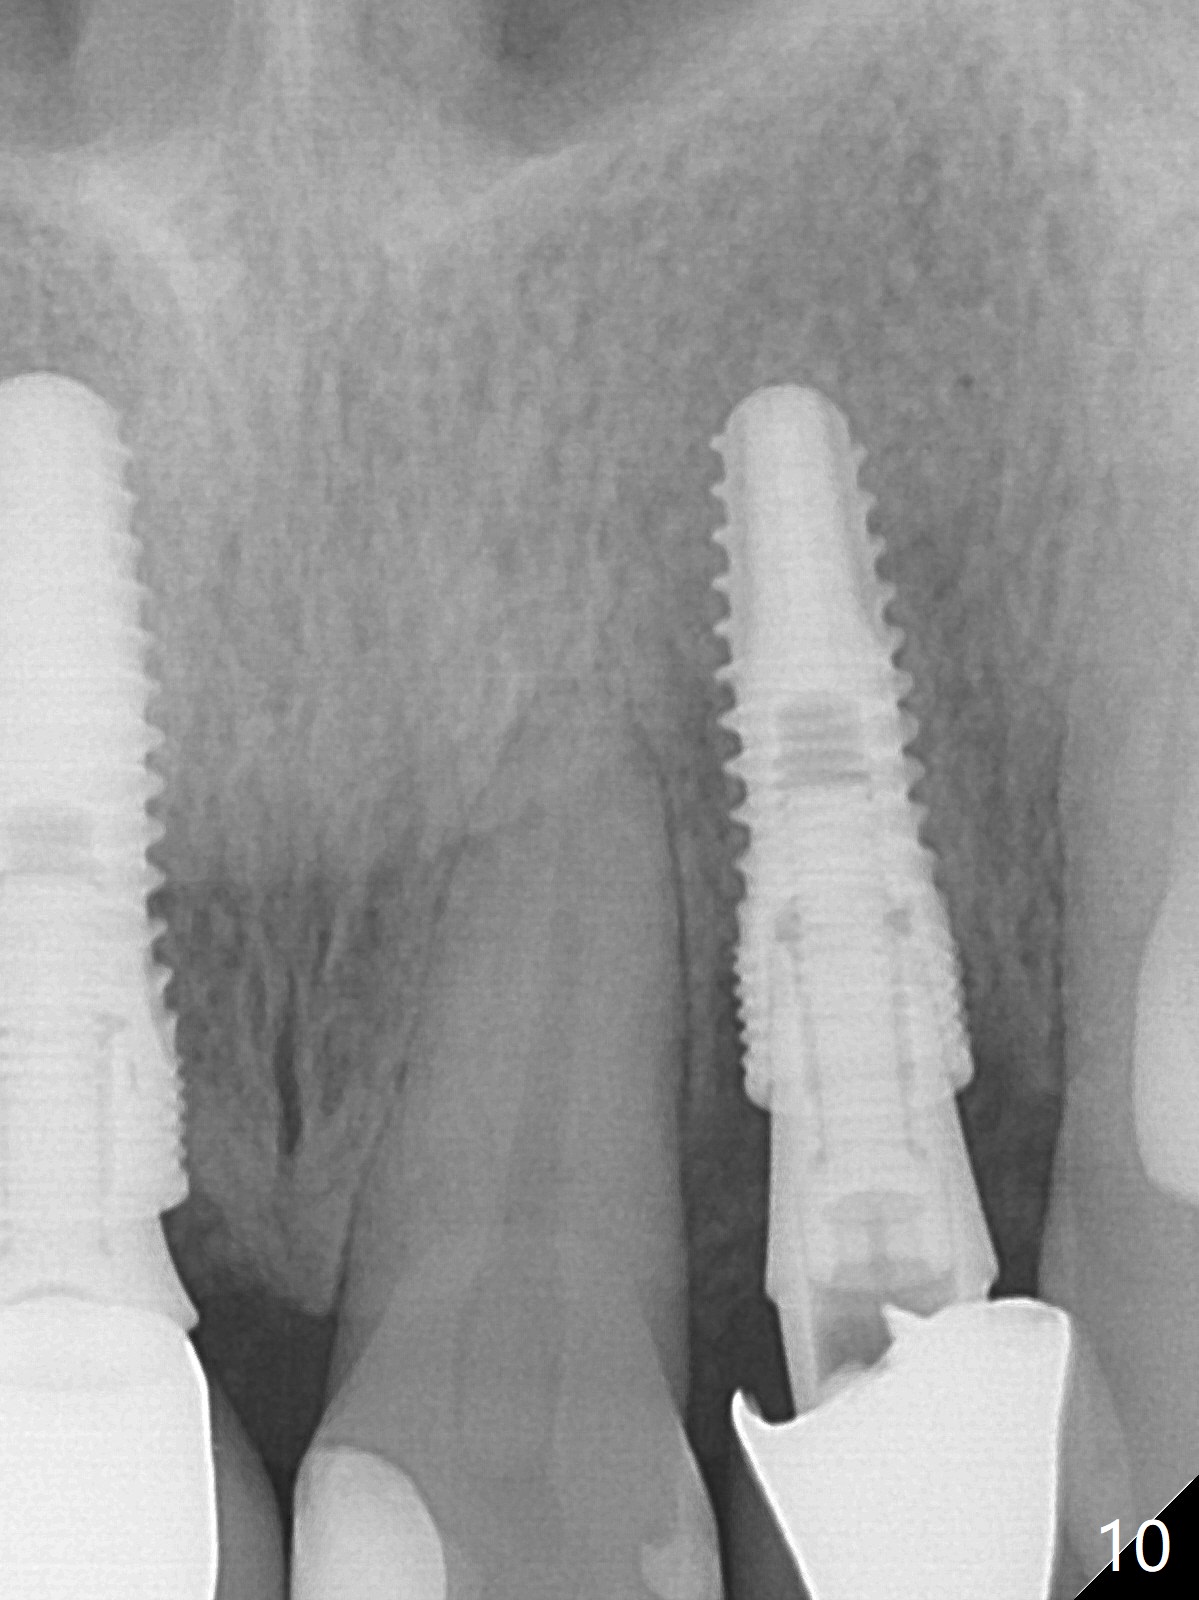

When the patient returns, the crown at #10 has displaced incisally (Fig.1,2 arrow). The initial depth is 15 mm (Fig.3, palatal gingival margin). After a 3.8x12 mm SM implant is placed (Fig.4), allograft is packed in the peri-implant space (*, as compared to Fig.3) and a 3.9x4(3) mm abutment is placed (A). More allograft is placed in the peri-abutment space (Fig.6 *). The existing crown (Fig.4,5 C) is hollowed, relined (R) and used as an immediate provisional (Fig.7-9). The patient is pleased with the appearance of the apically-repositioned provisional (Fig.7 arrow). She returns for impression 3.5 months postop (Fig.10). After change of abutment to 3.9x4(4.5) mm and new provisional, impression is retaken 5 months postop (Fig.11,12). It appears that the implant is palatally placed and a little large for the site (Fig.11 (B: buccal); Fig.12 (^: thin layer of the palatal plate)). If an angled abutment were used, a screw-retained crown might have been feasible. Due to the new provisional, the gingiva looks healthy when a permanent crown is cemented (Fig.13).